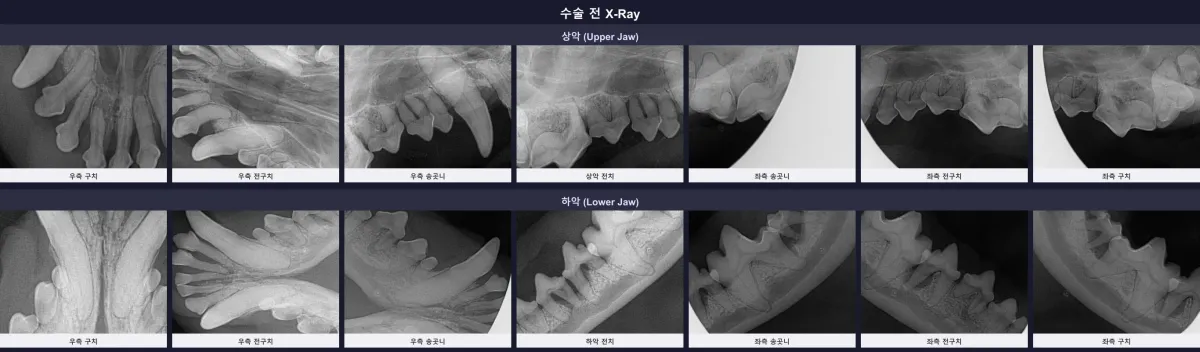

정확한 진단을 위해 마취 전 검사를 거친 후, 구강 방사선(X-ray) 촬영과 정밀 치과 CT 스캔을 진행했습니다. 검사 결과는 예상보다 심각했습니다. 대다수의 치아에서 치조골 흡수(ABL2 단계 이상)가 확인되었으며, 특히 108번, 109번, 208번, 209번 등 주요 어금니 부위에서는 치주 인대 소실 및 뿌리 끝 염증(PA3)이 관찰되었습니다. 치아를 지지해 주어야 할 뼈가 녹아내려 발치가 불가피한 상황이었습니다.

수술 전 환자의 전체 구강 방사선(X-ray) 판독 사진